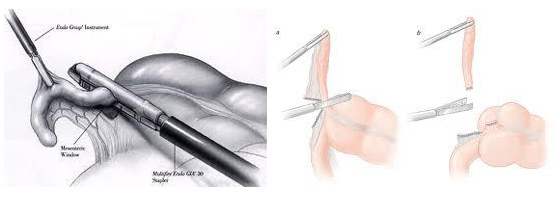

Χρησιμοποιώντας ένα σκληρό πλαστικό καθετήρα (trocar), ο χειρουργός εισέρχεται στην κοιλιά δημιουργώντας πνευμοπεριτόναιο. Έπειτα ένα λαπαροσκόπιο, (μικροσκοπικό τηλεσκόπιο συνδεδεμένο με μία βιντεοκάμερα) εισάγεται μέσω του trocar , δίνοντας στο χειρουργό μία μεγεθυμένη εικόνα των εσωτερικών οργάνων του ασθενούς σε μια οθόνη τηλεόρασης. Μέσω άλλων trocars ο χειρουργός χειρουργεί και αφαιρεί την φλεγμονώδη σκωληκοειδή απόφυση. Η όλη διαδικασία μπορεί να ολοκληρωθεί μέσα από τα trocars ή με επιμήκυνση σε μία από τις μικρές τομές για την είσοδο των trocars.